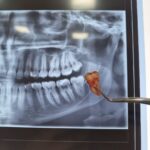

در بعضی موارد مراجعه دیرهنگام فرد برای کاشت دندان (ایمپلنت) یا وجود کیست و تومورهای دهانی منجر به از بین رفتن فضای مناسب و کم شدن قطر و ارتفاع استخوان فک میشود که در این حالت، دندانپزشک قبل یا همزمان با جایگذاری فیکسچر، با استفاده از پودر و بلاک استخوانی و ممبرین (بایومتریالها) استخوان را بازسازی کرده تا شرایط مناسب برای قرارگیری ایمپلنت مهیا گردد. در این مواقع طول درمان بیمار (آماده شدن استخوان برای جایگذاری ایمپلنت) بسته به شرایط بیمار از ۳ تا ۶ ماه طول میکشد و دندانپزشک به کمک عکسهای رادیوگرافی میتواند روند درمان را دنبال کند و بهترین زمان را برای کاشت ایمپلنت تشخیص دهد.